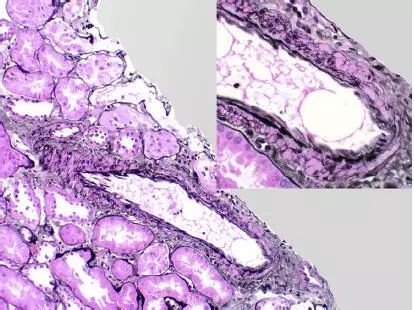

CNI肾毒性导致的血管收缩无形态学变化。急性CNI肾毒性特征包括:近端肾小管上皮细胞空泡化,大小一致;血管损伤,平滑肌细胞丢失;肌细胞胞浆空泡化;细胞坏死或凋亡退化。肌细胞损伤最终发展为局灶性结节性玻璃样变和透明样变,可延伸至小动脉和动脉血管壁整个中层。CNI肾毒性还可引起血栓性微血管病变(TMA),主要累及小动脉和肾小球毛细血管袢。慢性CNI毒性特征为:条状间质纤维化,肾小管萎缩。

图4 CNI肾毒性结节性透明样变延伸至肾小叶间动脉中层(Jones 银染)

图5 CNI肾毒性结节性透明样变延伸至动脉中层(PAS染色)

图6 CNI肾毒性条状肾间质纤维化(Jones 银染)